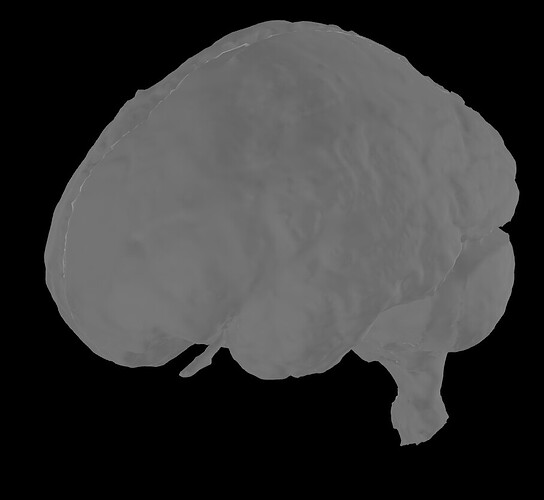

I am finding some quirky behaviour in the surface extraction tool from FEM model. When I display the FEM model, I obtain, for example, the right compact mask:

Then, I extract the surfaces, but what I now obtain as compact seems very different: